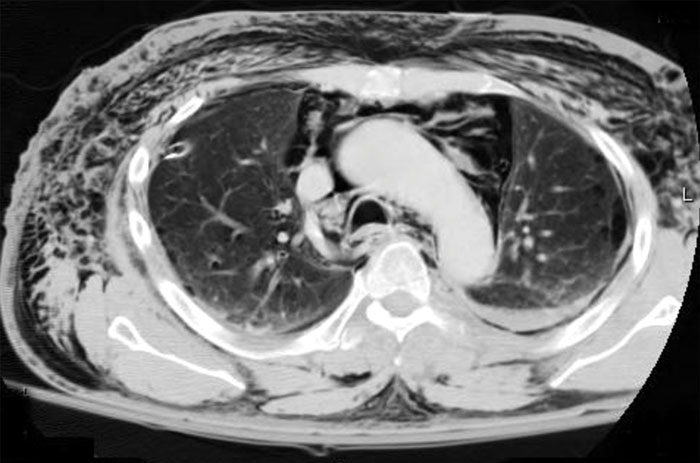

Clinical-Pneumomediastinum.jpg

Diagnosis and Treatment of Pneumomediastinum A 22-year-old female arrives in your trauma bay in respiratory distress. She appears slightly anxious and is mildly tachypneic. Vital signs are as follows